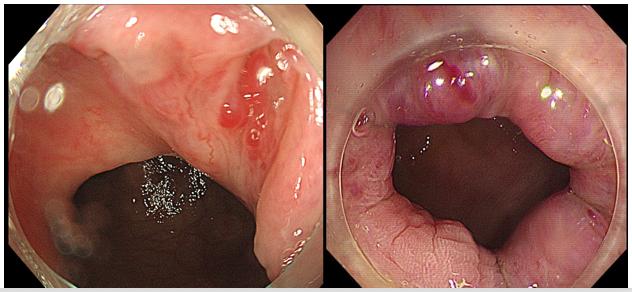

■透明帽辅助下内镜下硬化术

✔是在2015年报道的一种更方便、安全、高效的内镜下微创治疗痔疮和粘膜脱垂的新技术。透明帽辅助下内镜下硬化术是非手术疗法中最有效的选择,特别适合有出血风险的患者。

✔CAES利用透明帽辅助肠镜,在内镜直视下操作,可以充分暴露肛直肠病变,注射点一般不出血,术后无疼痛不适。有效避免传统硬化术的医源性损伤。

基本原理:将硬化剂注射到痔核黏膜下或痔核组织中,通过硬化剂的渗透,硬化剂与痔核组织中的微小血管密切接触,导致痔血管闭塞、痔核组织纤维化,从而达到止血和改善脱垂等作用。

适应症:Ⅰ-Ⅲ度内痔,直肠黏膜脱垂,内镜下切除肛门赘生物和瘤性病变前的基底预防出血治疗。尤其对于全身状态差,合并难以控制的痔疮出血,也不具有外科手术条件的患者。